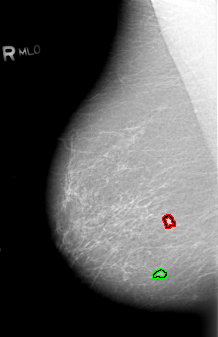

B_3010_1.RIGHT_MLO

FILE: B_3010_1.RIGHT_MLO.OVERLAY

TOTAL_ABNORMALITIES 2

ABNORMALITY 1

LESION_TYPE MASS SHAPE IRREGULAR MARGINS ILL_DEFINED

ASSESSMENT 4

SUBTLETY 3

PATHOLOGY MALIGNANT

ABNORMALITY 2